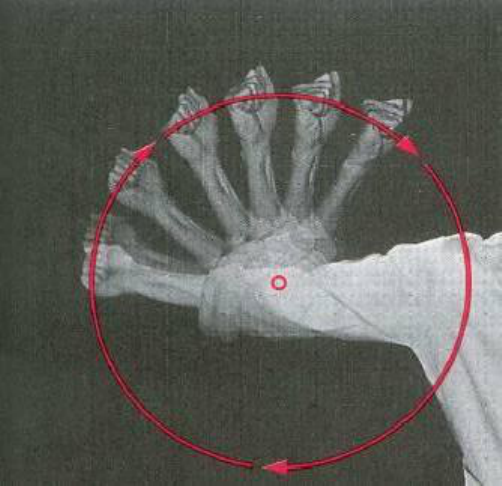

Metacarpianos e Falanges

– Na face dorsal da mão.